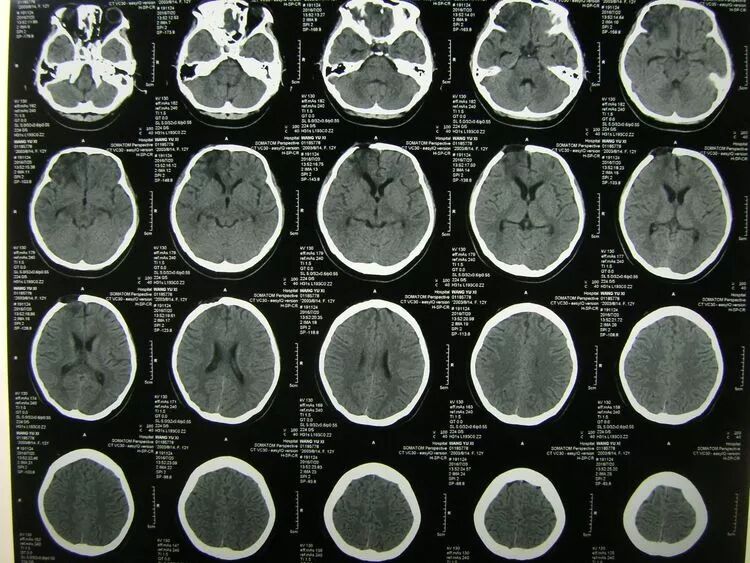

患儿女,12岁,头部车祸伤2小时入院,浅昏迷状,右额部纵形锯齿状裂口,前自眉弓延伸至发际内,可见骨折裂隙。右瞳孔欠规则。

CT示:

右额叶脑挫裂伤,蛛网膜下腔出血,颅内积气,额骨及前颅底骨粉碎骨折,基底池模糊。